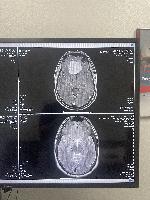

Another MRI top view